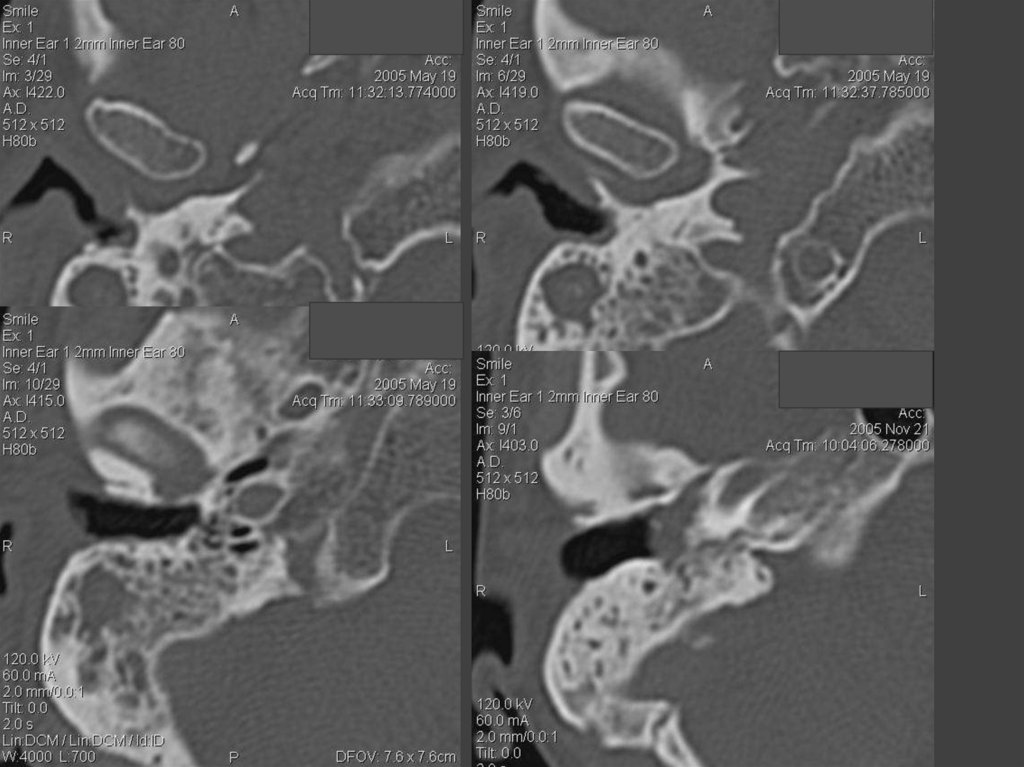

81. Внутриканальная акустическая невринома (по Swartz J.D. and Harnsberger H.R. 1998)

82. Акустическая невринома

83. Акустическая невринома